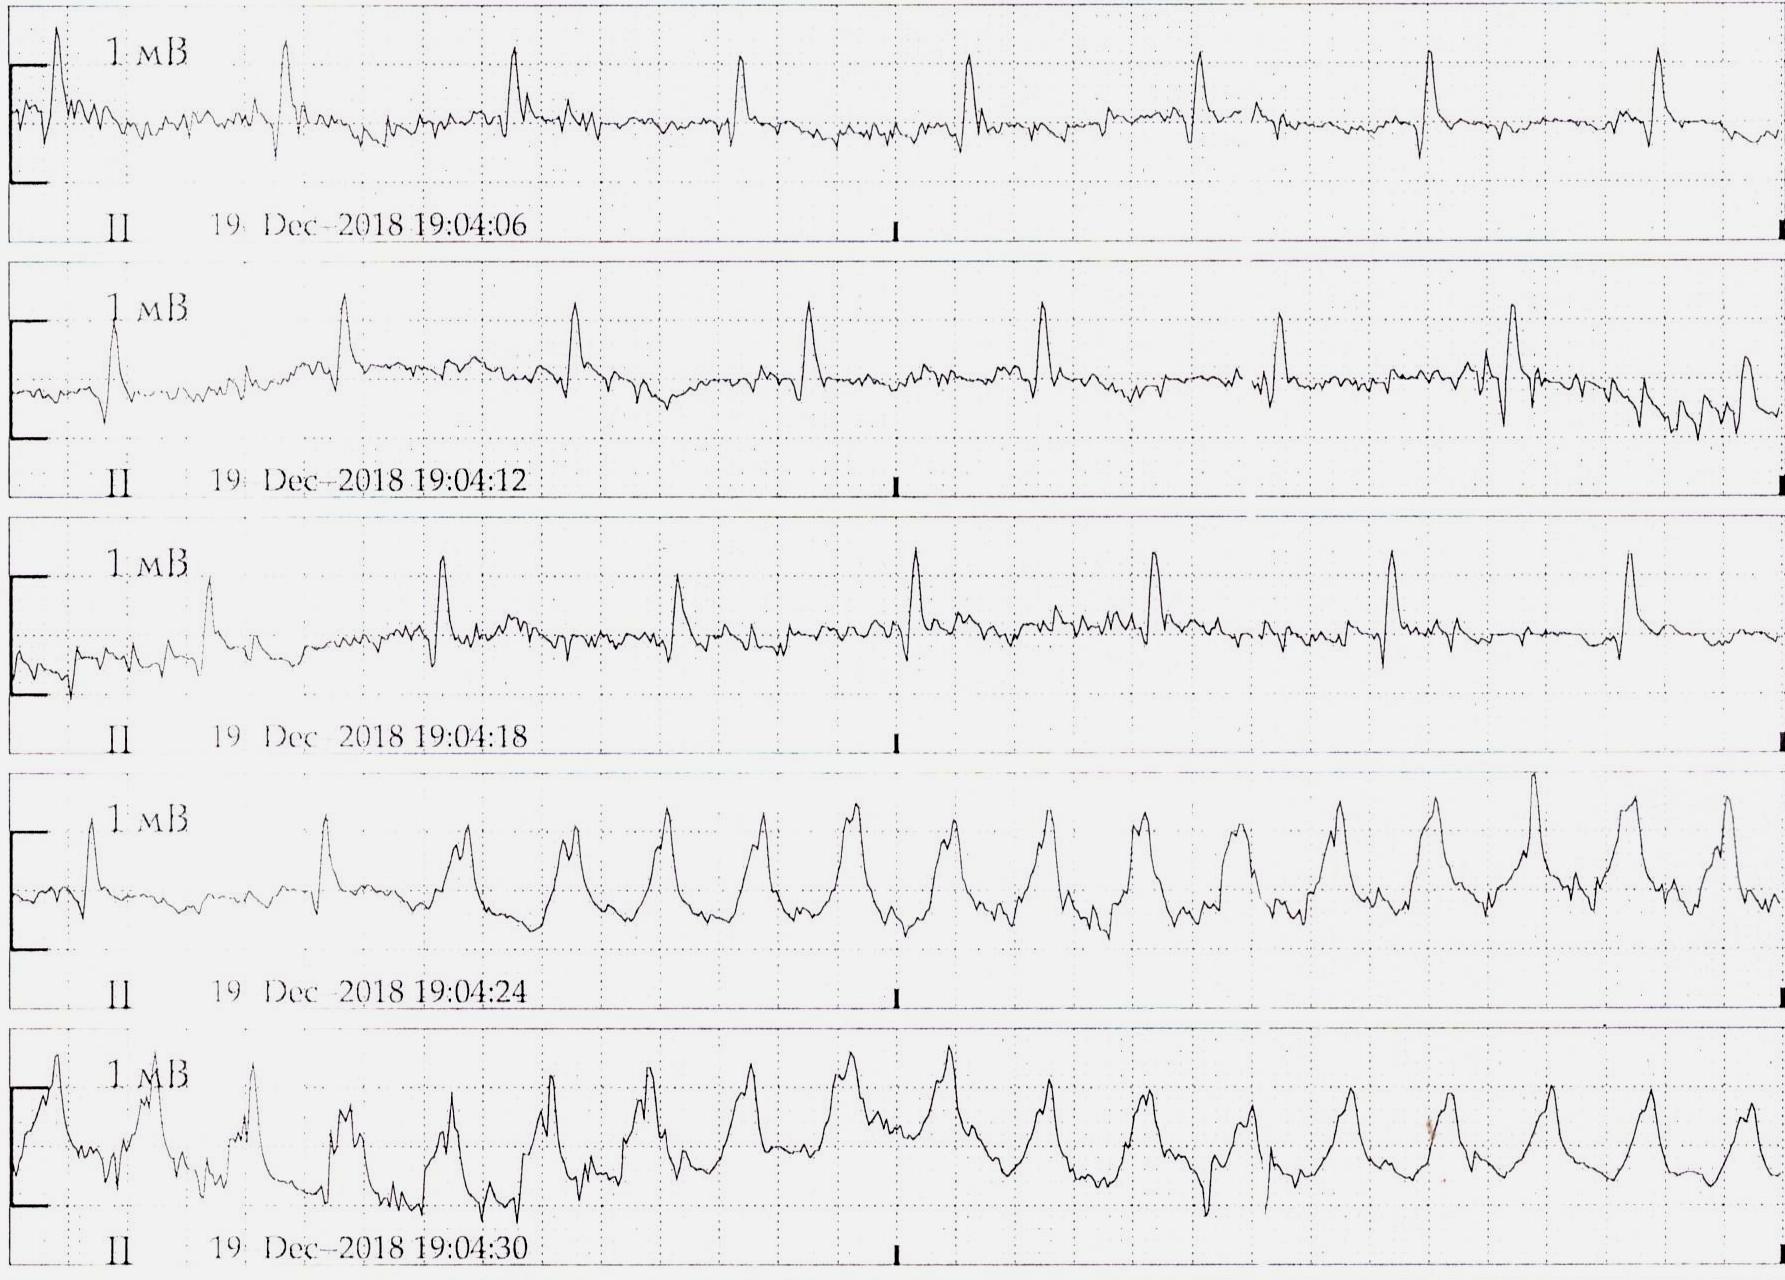

Пируэтная, хоть и пируэт не классический

Вложения:

1.jpg

1.jpg [ 263.14 KiB | Просмотров: 38272 ]

2.jpg

2.jpg [ 241.86 KiB | Просмотров: 38272 ]